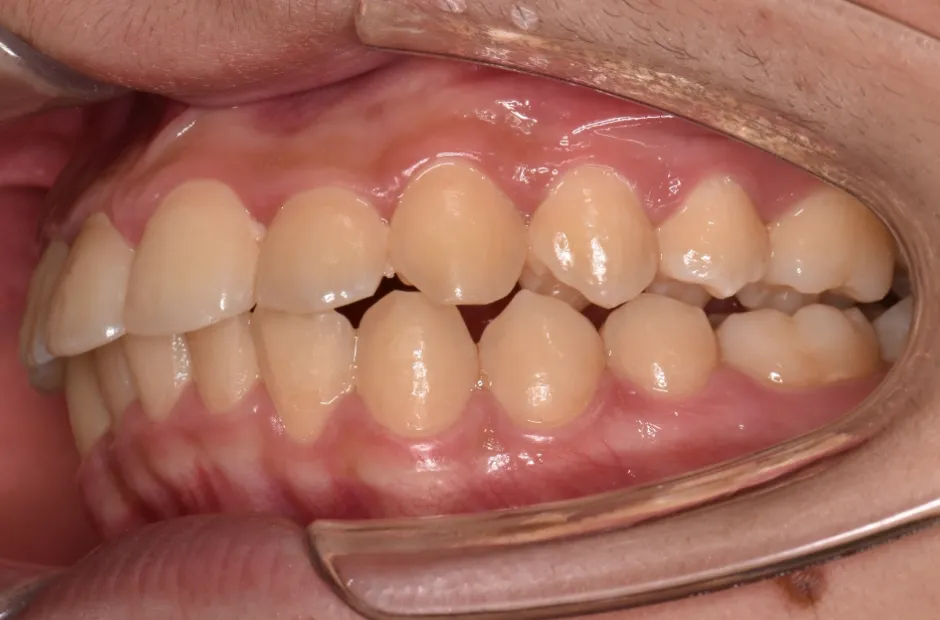

治療症例

ブラケット矯正

前歯部反対咬合

| 診断名・主訴 | 前歯部反対咬合 |

|---|---|

| 年齢・性別 | 14歳・男性 |

| 治療期間・回数 | 1年2か月 |

| 治療に用いた主な装置 | ブラケット矯正 |

| 抜歯部位 | なし |

| 治療費 | 60万円(税抜) |

| リスク・副作用 | 装置による違和感・疼痛・歯肉退縮・歯根吸収・虫歯のリスクなど |

治療後